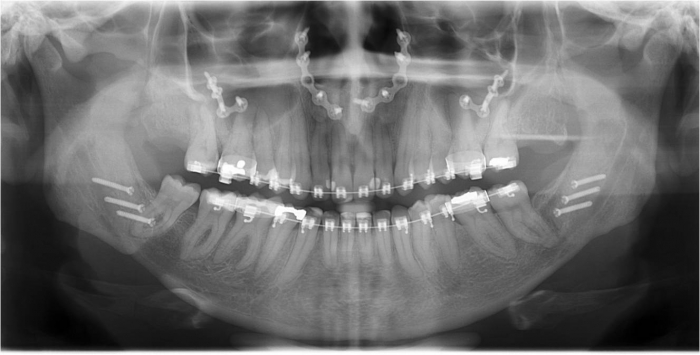

Raio x inicial

Raio x após a cirurgia